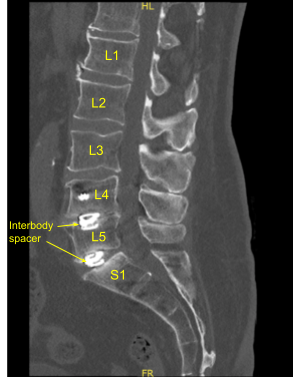

This patient previously underwent L4 to S1 minimally invasive transforaminal lumbar interbody fusion. They did well and recovered, however subsequently developed recurrence of their low back pain, had various injections and nonsurgical treatments including a sacroiliac joint fusion.

However, their back pain only worsened. Imaging showed loosening of bilateral pedicle screws and signs of pseudarthrosis. Surgery was recommended to stabilize the lumbar spine. The risks, benefits, alternatives and potential complications of the surgery were explained to them.

The skin was opened with a #10 blade Scalpel. Hemostasis was obtained with bipolar electrocautery. Bovie monopolar and Cobb elevator were used to perform subperiosteal dissection exposing posterior elements of the spine from L4 to sacrum including previous spinal hardware pedicle screw-rod construction from L4 to S1. Self-retaining retractors were placed. Locking caps were removed x6 on both sides. The rods were removed. The fusion was explored and found to be inadequate.

Loosening of bilateral sacral screws was confirmed and they were removed. We placed the neuronavigation array and fixed it rigidly to the posterior superior iliac crest with two Schanz pins.

The patient was draped sterilely. CT scan was obtained, and data was transferred to the neuronavigation computer. Neuronavigation techniques were used to reposition and replace bilateral sacral screws which were upsized both in diameter and length until tight.